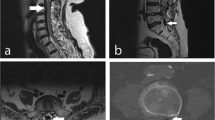

A 72-year-old woman, with no significant past medical history, presented with a 1 year history of thoracic back pain and a 2 week history of progressive lower extremity weakness. Neurological examination revealed MRC grade 3/5 power including and distal to the L2 myotome. She had reduced pin-prick sensation below L1 bilaterally. Reflexes were brisk in the lower limbs and both planters were upgoing. Neurological examination of the upper limbs was normal. Magnetic resonance imaging (Fig. 1) and a CT scan (Fig. 2) demonstrated a central calcified disc herniation at the level T9–T10 level causing spinal cord compression with T2 signal change in the spinal cord. The calcified disc prolapse occupied more than 60 % of the cross-sectional area of the spinal canal.